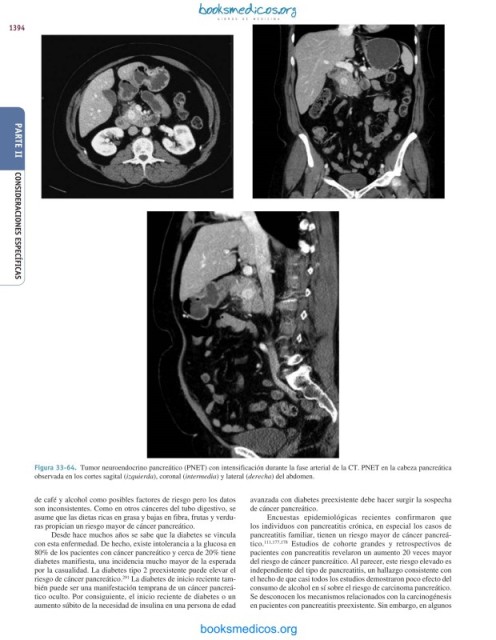

Figura 33-64. Tumor neuroendocrino pancreático (PNET) con intensificación durante la fase arterial de la CT. PNET en la cabeza pancreática

observada en los cortes sagital (izquierda), coronal (intermedia) y lateral (derecha) del abdomen.